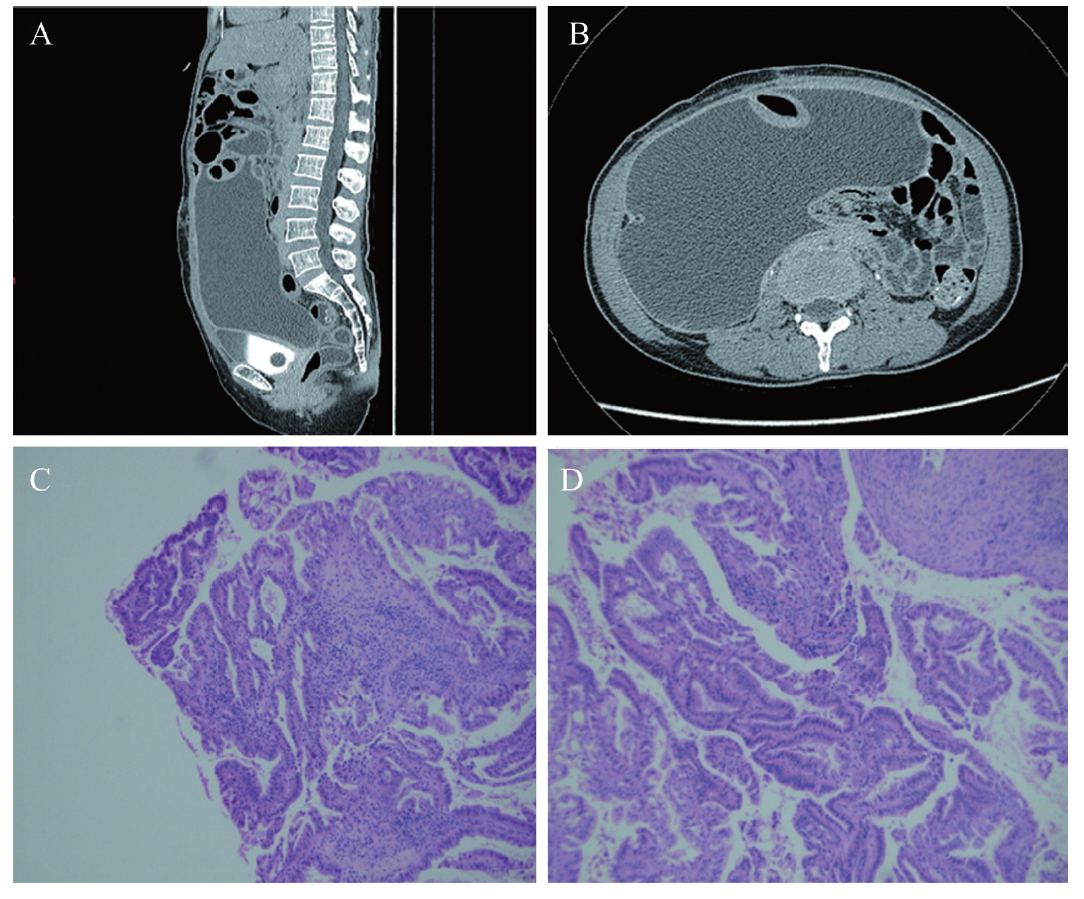

入院当日血常规:血红蛋白100 g/L,红细胞3.54×1012/L,白细胞5.84×109/L,中性粒细胞0.85,淋巴细胞0.09。CRP 66.2 mg/L,白蛋白39.9 g/L。肝、肾功能及结核相关检查未见异常,降钙素原和肿瘤标志物(癌抗原125、人附睾蛋白4、癌抗原153、糖链抗原199、癌胚抗原、甲胎蛋白)亦未见异常。入院次日予腹腔穿刺引流术,穿刺出澄清、淡黄腹水,第1次腹水检查示:李凡他试验(-),腹水肌酐、癌胚抗原、腺苷脱氨酶(ADA)、抗酸杆菌涂片均未见异常;腹水白蛋白22 g/L,甘油三酯< 0.1 mmol/L,癌抗原125 253.3 kU/L。胸腹增强CT:①腹腔大量积液,右侧髂血管旁囊性病灶,未排除淋巴囊肿;②肠淤积;③乙状结肠直肠交界区局部肠壁增厚并强化,见图1A、B。腹水液基薄层细胞学检测(TCT)镜下见炎症细胞及少量间皮细胞,未见异型细胞。

图1 一例卵巢癌淋巴切除术后顽固性淋巴漏的辅助检查结果

A:腹部增强CT(矢状位);B:腹部增强CT(横断位);C、D:病理玻片会诊结果示卵巢交界性子宫内膜样腺癌(HE染色,×200)

影像科:CT提示大量腹腔积液,右侧髂血管旁囊性病灶;影像学上考虑卵巢癌术后并发症引起的腹腔假性黏液腺癌,但CT不易鉴别腹水性质为浆液性或黏液性。

肿瘤科:外院病理提示卵巢黏液性囊腺癌,但未明确是否为原发,需完善免疫组织化学(免疫组化)检查明确来源;粪潜血(+),且CT提示肠管部分增厚(图1A、B),建议完善PET/CT、消化内镜排除消化道肿瘤。